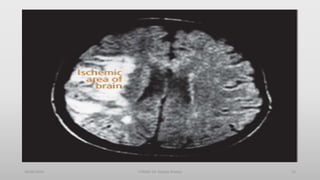

Ischemic – Thrombotic Stroke

Lumen of the blood vessels narrow – then becomes

occluded – infarction

Associated with HTN and Diabetes Mellitus

>60% of strokes

50% are preceded by TIA

Lacunar Stroke: development of cavity in place of infarcted

brain tissue – results in considerable deficits – motor

hemiplegia, contralateral loss of sensation or motor ability

Diagnosis

• CT Scan

• MRI